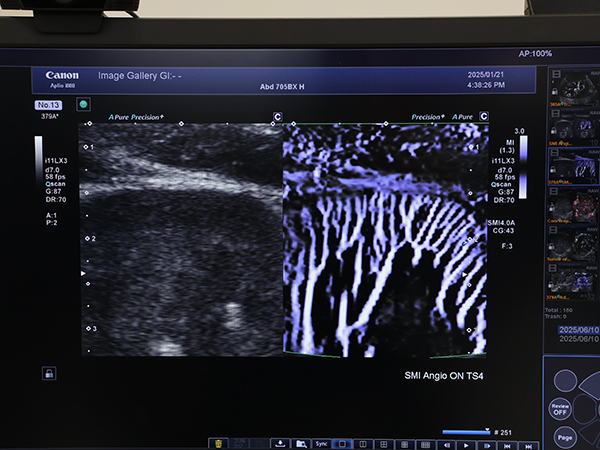

●超音波:「SMI Angio mode」により微細・低流速な血流をより明瞭に描出

ハイエンド装置として進化を続けるAplio i800 / Prism Editionでは,微小血管・低流速の血流を可視化する独自技術Superb Micro-vascular Imaging(SMI)に,新たに「SMI Angio mode」が追加された。血流信号の特徴量を解析しブルーミングを低減する信号処理技術により,血流パターンの視認性を向上した画像をリアルタイムに描出可能になり,より微細な血流像が明瞭に表現されるようになった。

微細・低流速血流をより明瞭に描出する「SMI Angio mode」